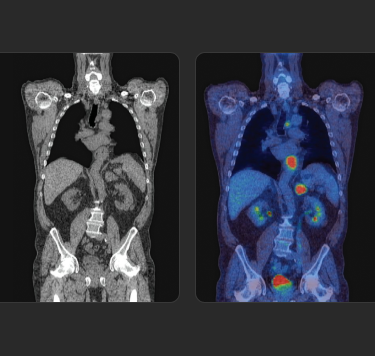

La Terapia con RadioLigandi (RLT) è un trattamento di precisione che rappresenta un'innovazione importante in ambito oncologico.

Scopri la RLT, le basi di questa forma di medicina di precisione e come Novartis sta gestendo la somministrazione continua della RLT ai pazienti in tutto il mondo.